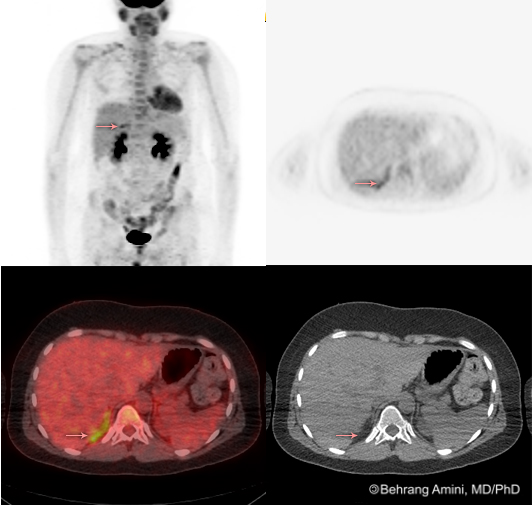

Brown Fat Pet/ct